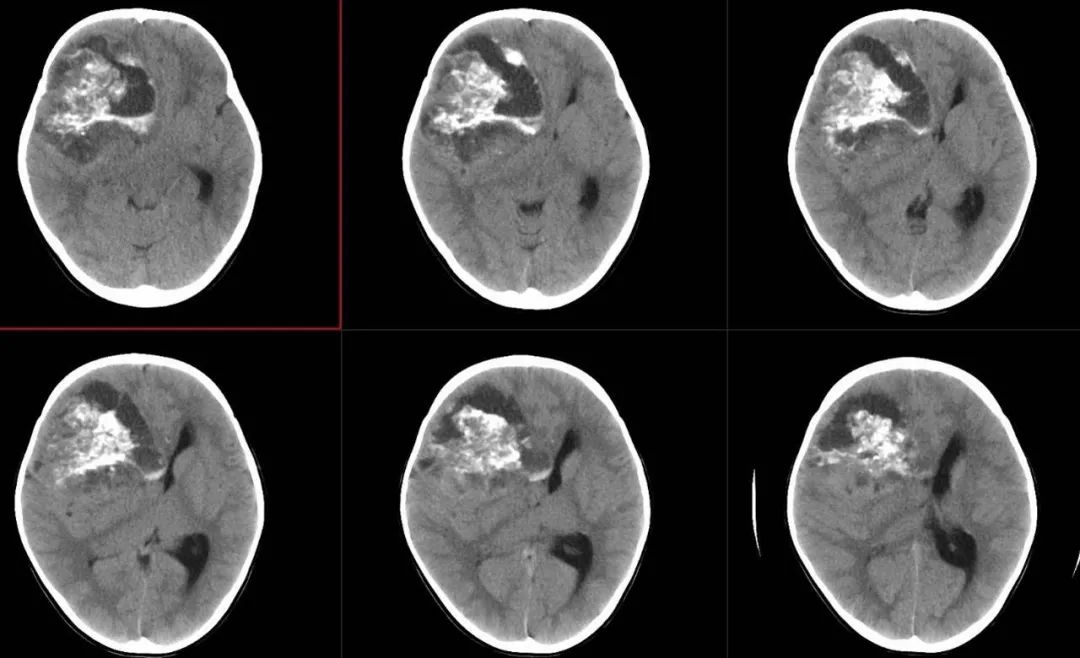

术前影像

术前颅脑CT囊实性占位